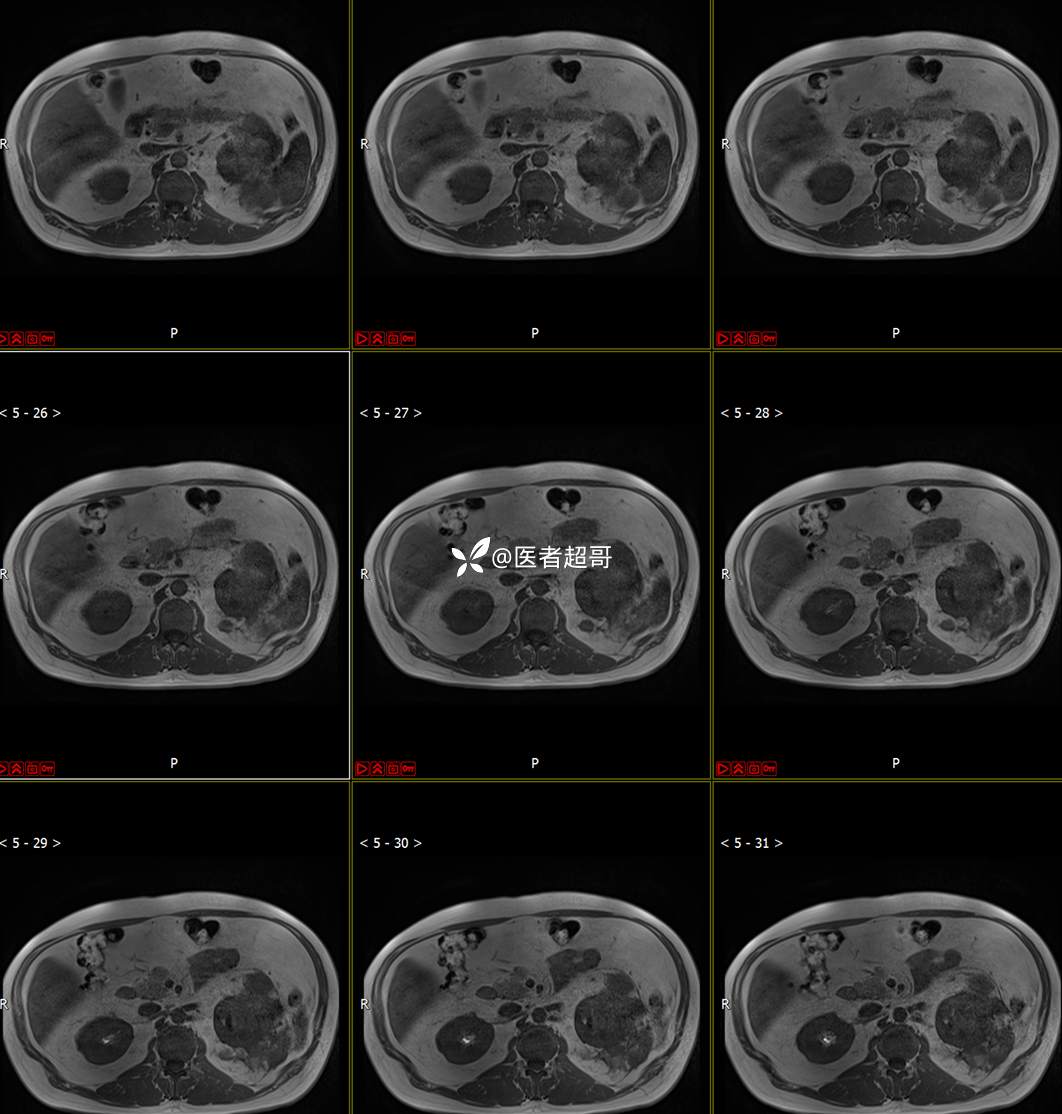

主 诉:查体发现左肾肿物9天。

现病史:患者9天前于附属医院行常规腹部CT检查时,发现左肾占位性病变并肾周脂间隙软组织增多,自述无明显腰腹部不适,无尿频、尿急、尿痛及肉眼血尿,未予特殊治疗,患者近期无头晕头迷,胸闷气急,腹胀腹泻及其他部位明显不适,遂至我院就诊,门诊以“肾肿物”收入院,患者自发病以来,精神可,睡眠饮食可,大便正常,体重无明显减轻。